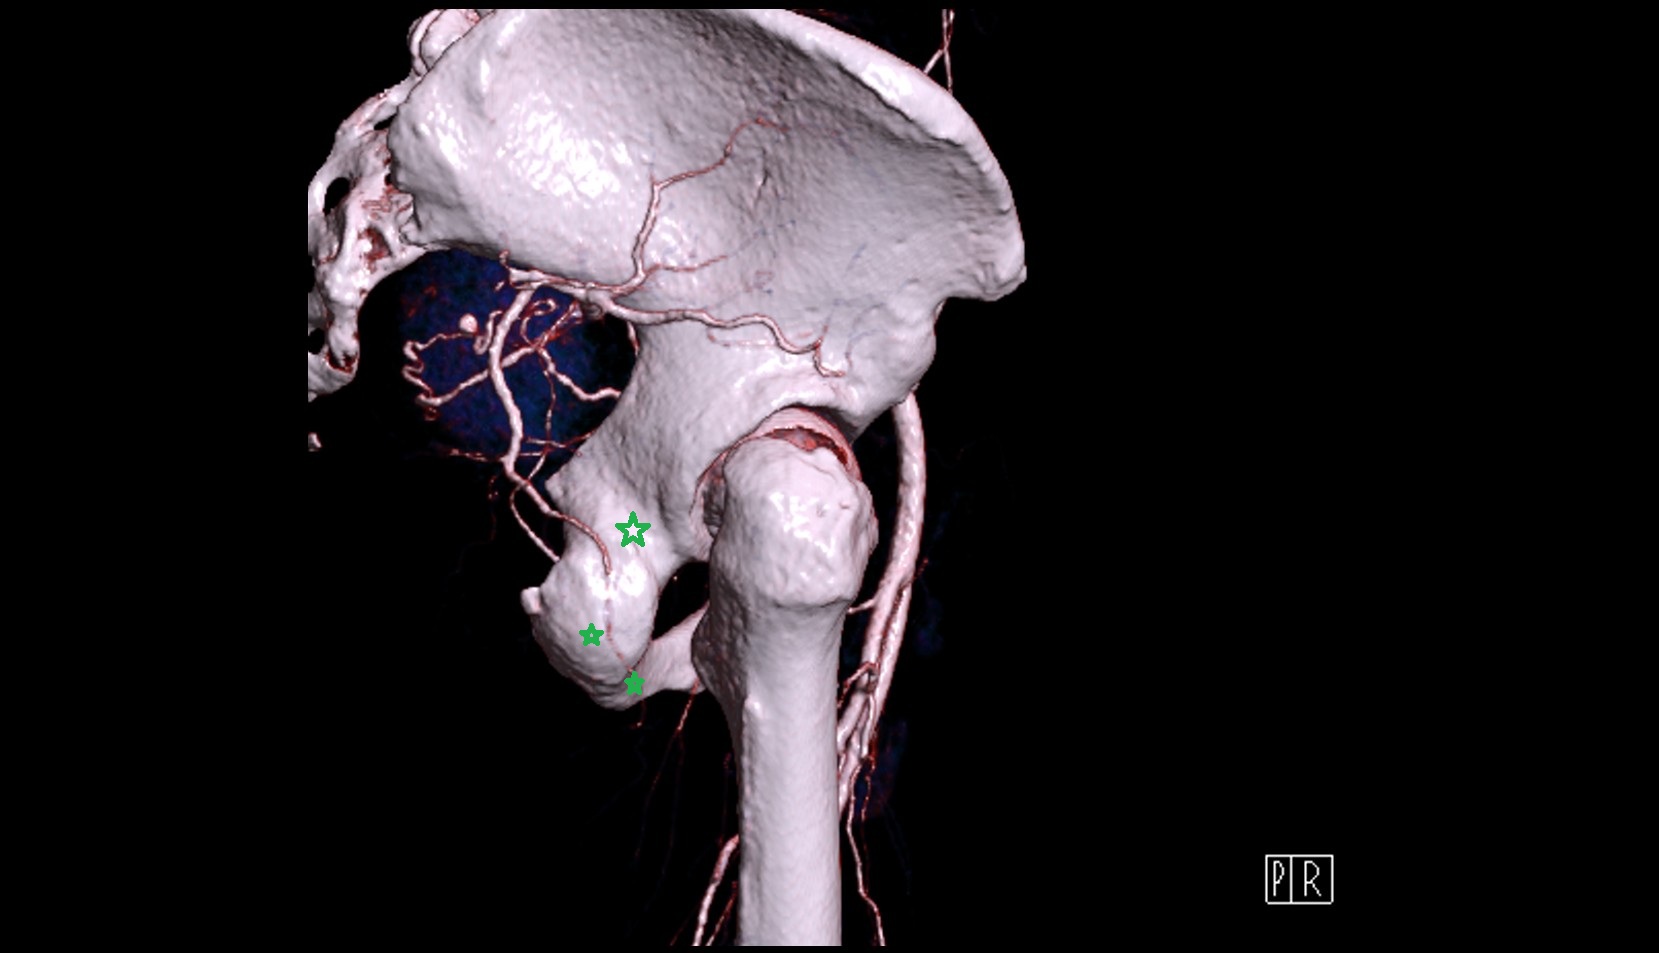

- Lateral circumflex femoral artery

- Deep femoral artery (profunda femoris)

- External iliac artery

- Femoral artery

- Internal iliac artery

- Medial circumflex femoral artery

- Obturator artery

- Pudendal artery

- Superior gluteal artery